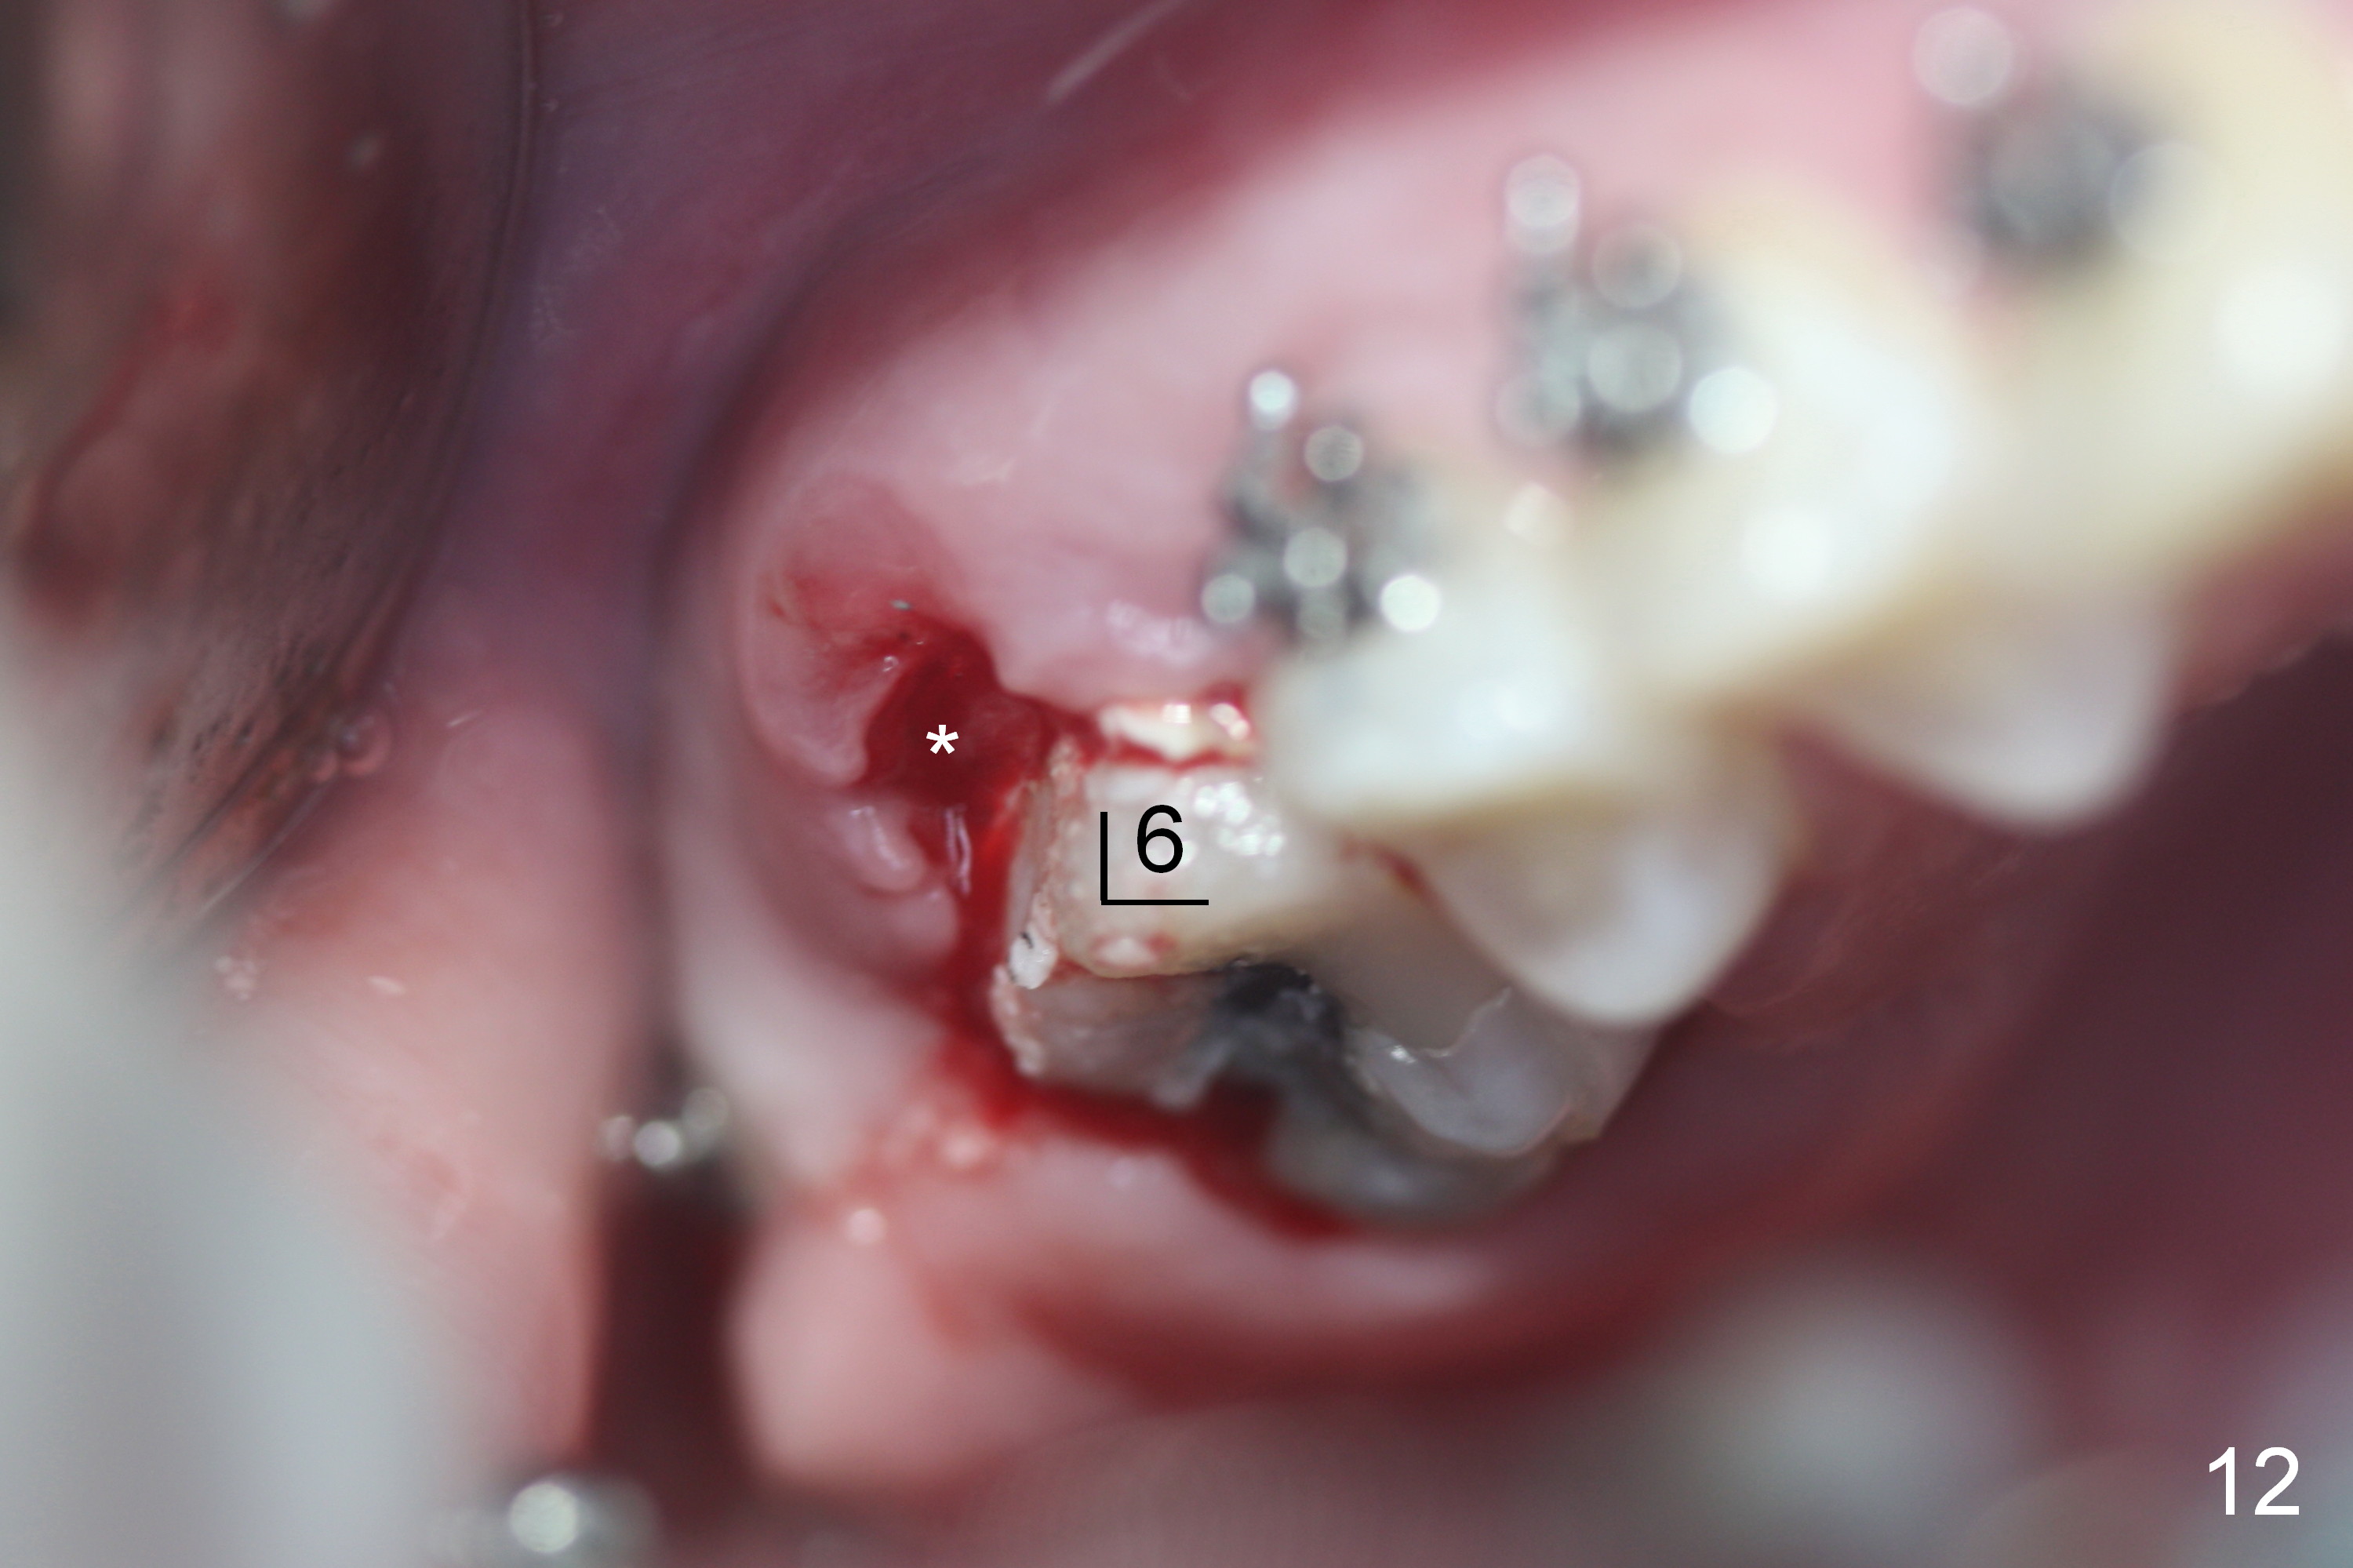

On March 9, 2016 (11.5 months of treatment), periodontal abscess develops around UR6 (Fig.11 (palatal view) *). It appears that the molar band as well as the buccal tube (Fig.12 *) is embedded into the gingiva. One week after band removal (as well as posted wire and closed coil springs), the infection resolves (Fig.14). As compared to preop Panoramus (Fig.13), the upper arch distalization is mainly at the crown level (Fig.4 arrows). The miniimplants should be placed higher (at the zygomatic arch); the post should be taller. Therefore the roots can be distalized as well (click the link below).